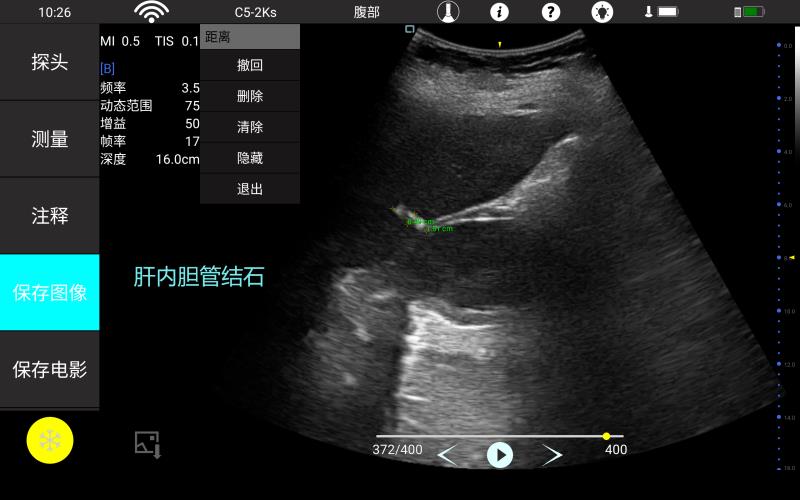

• 大凸

腹部

肾脏

妇科产科

心脏

肺等